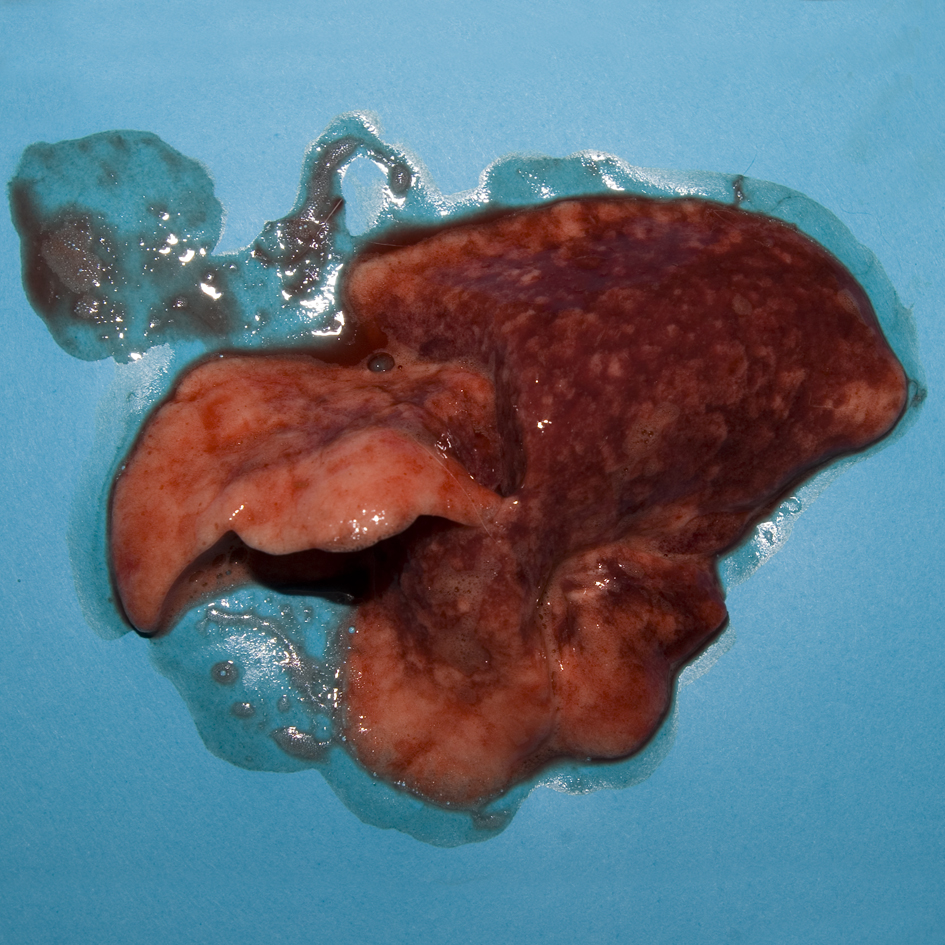

Pulmonary congestion and oedema

Pulmonary haemorrhage and oedema are features of RHD although, macroscopically, it can be difficult to differentiate agonal changes, such as alveolar collapse, congestion, and alveolar oedema from lung pathology. In this confirmed case of RHD, fibrin thrombi were seen in occasional small capillaries and venules on histopathological examination.